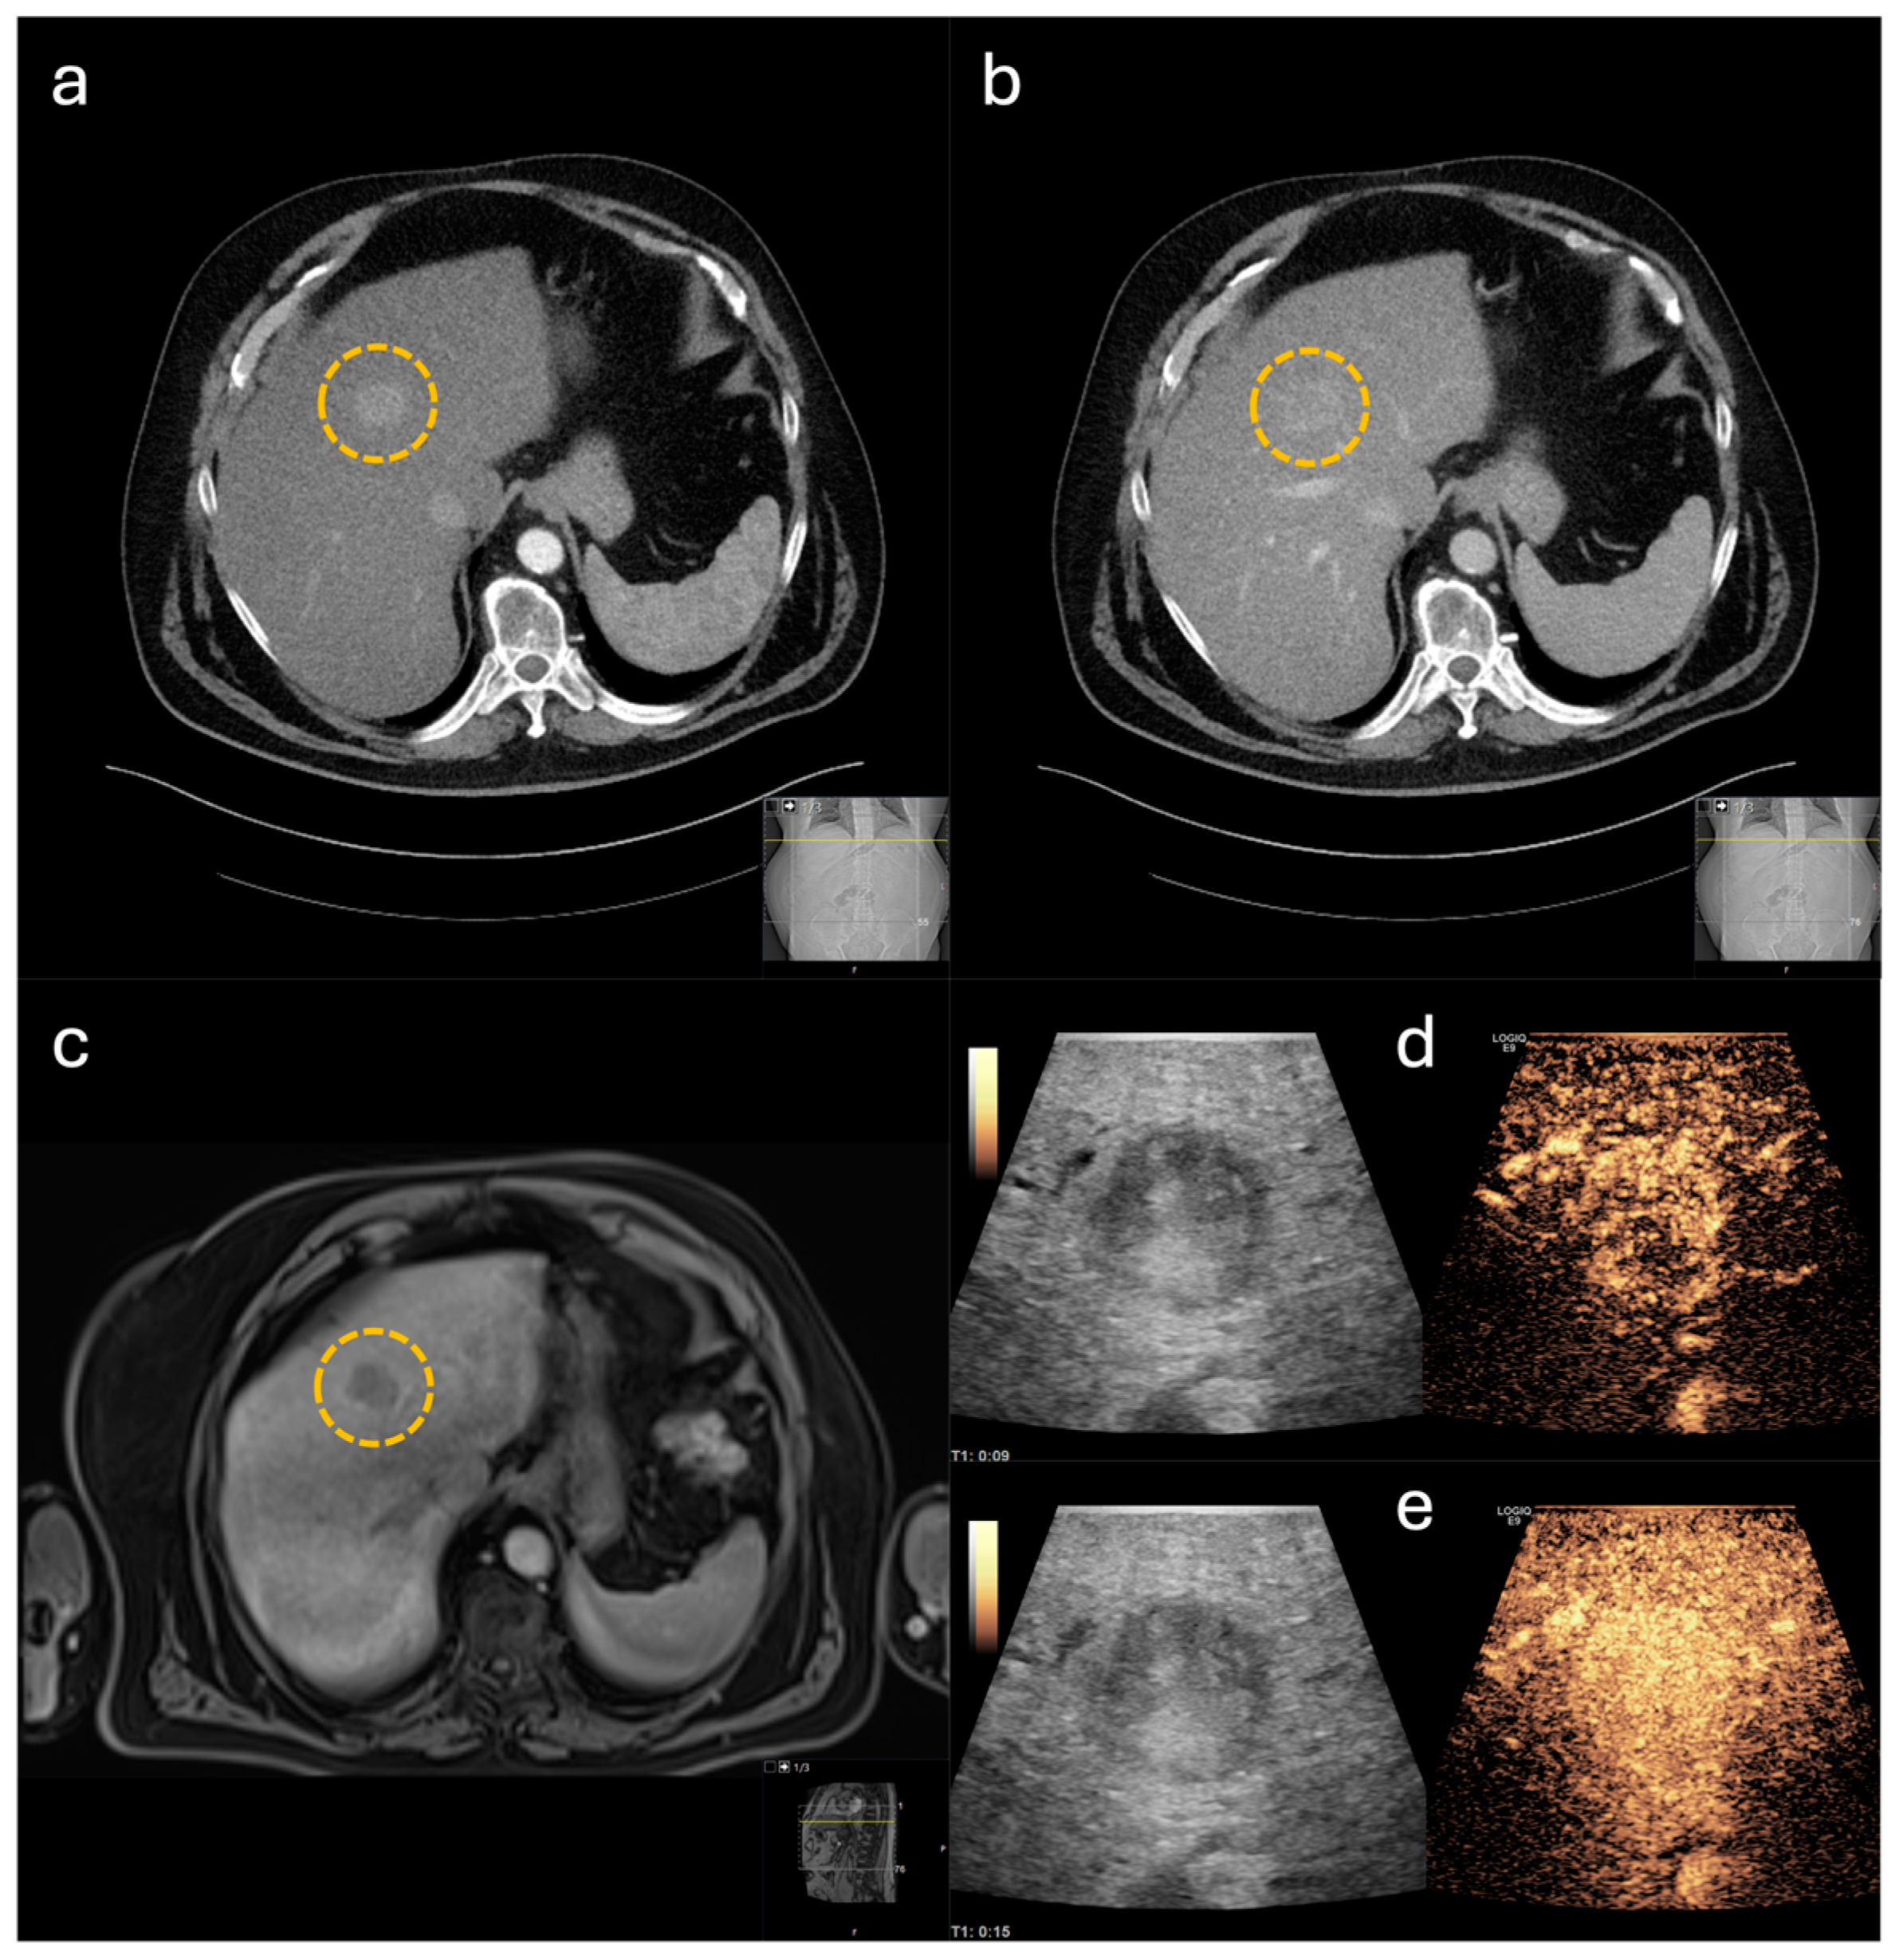

3.3. Accuracy of CE-IOUS